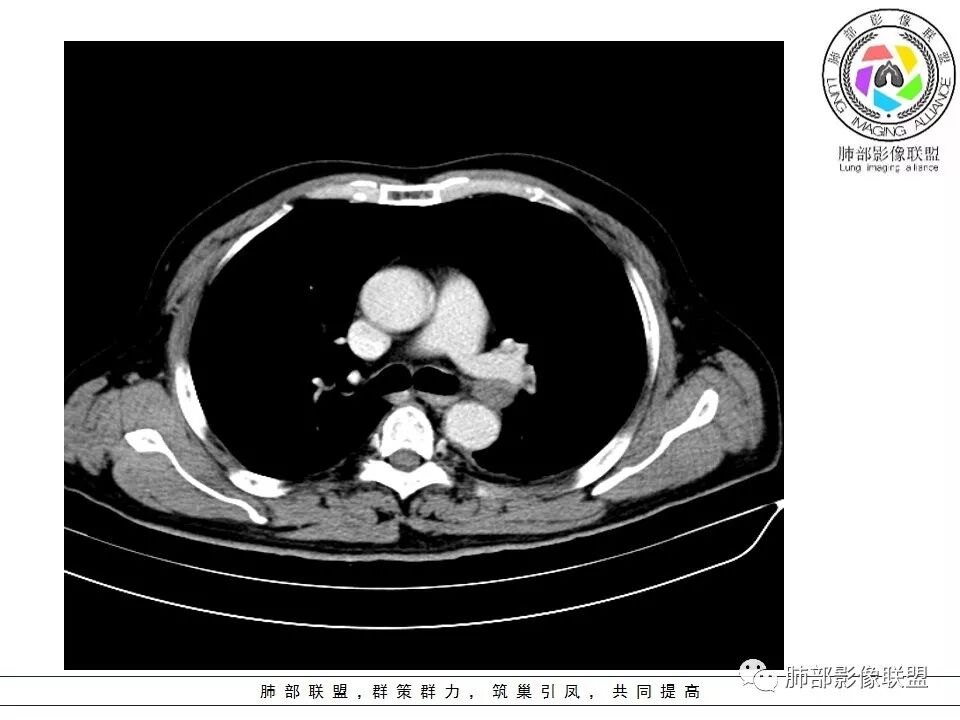

老年男性咳嗽,左下近肺门团块影,不规则强化伴坏死,左下肺静脉、支气管旁淋巴结转移受压、并侵犯左下支气管,考虑鳞癌,鉴别小细胞。

男,70岁,左下肺肿块影,分叶,增强有较大范围坏死,左肺门肿块影,跨叶,包绕支气管与肺门血管,致其狭窄考虑为淋巴结肿大,综合考虑为恶性肿块,鳞癌并左肺门淋巴结转移

老年男性,咳嗽主诉,胸部ct左侧肺门新生物,支气管阻塞,不均匀强化,伴淋巴结肿大,考虑鳞癌,鉴别小细胞肺癌。

老年男性,左下占位,类圆丶浅分叶,无毛刺及胸膜凹陷征,各支气管狭窄,增强不均匀强化,左肺门淋巴结肿大考虑恶性,小>鳞

患者老年男性,以咳嗽就诊,胸CT:左肺下叶占位,病灶呈膨胀性生长,左肺下叶气管明显狭窄,病灶边缘光滑,并可见分叶,增强可见病灶内低密度区,病灶边缘强化。考虑恶性,鳞?肉瘤?

左下肺团块影,不规则强化伴坏死,左下肺静脉、支气管旁淋巴结转移,并侵犯左下支气管,考虑恶性病变,小细胞?

左肺主支气管下肿块,病变包绕并向腔内生长,无阻塞性肺炎,内部可见穿行血管,增强后可见实性明显强化,纵隔淋巴结肿大,老年男性,考虑:神经内分泌癌(类癌、小细胞癌),淋巴瘤,鳞癌

病史:男,70岁,咳嗽;影像:肺门淋巴结,淋巴结内血管毛糙不规则,静脉期,转移大,左心房左下静脉下支是否有累及。主体病灶,呈扇形,沼泽样,指状突起。肺气肿并不明显,左侧少许,左上叶支气管狭窄,肺窗点状凸起,纵膈窗并没有,考虑淋巴结压迫所致。老王曾经说过,小细胞来不及跑得快,胸膜目前没有积液是否是这个原因?诊断:恶性,小细胞肺癌;鉴别:鳞癌,不太像,其他神经类分泌恶性肿瘤;处置:经皮穿刺或EBUS。

左下肺占位性病变,伴肺门淋巴结肿大,强化示不均匀明显强化,可见边界不清坏死区,考虑恶性肿瘤!病灶缺乏分叶及毛刺,整体圆顿,病理倾向大细胞!

左下肺肿块,不均匀强化,其内可见坏死或粘液,更多考虑坏死,左下肺支气管堵塞,左肺门多发肿大淋巴结,左下肺癌,鳞癌可能性大鉴别于小细胞癌

病灶从外向里长,气管狭窄,血管受侵犯,肺门纵膈淋巴结肿大,考虑恶性,首先考虑小细胞癌

左下肺占位伴肺门淋巴结肿大,病灶呈膨胀性生长,左肺下叶气管明显狭窄推移,病灶边缘光滑,并可见分叶,增强可见坏死,病灶边缘强化,阻塞性肺炎不明显,恶性没问题,考虑低分化腺癌,鉴别神经内分泌肿瘤,无冰冻感觉,坏死明显,小细胞不支持,排除大细胞与类癌

老年男性,症状轻。左肺下叶类圆形肿块,边界清楚,分叶不明显,其内无空泡征,边缘无毛刺及胸膜牵拉,远端无阻塞性肺炎。左肺门影增大。增强扫描左肺下叶肿块可疑轻度强化(无平扫对比),局部见小尾巴征。左肺门区见不规则形团块,似多个结节融合,肺动脉受压穿行于病灶中,形成冰冻肺门感觉,局部层面似见肺门区团块与左肺下叶肿块相连。综合考虑小细胞肺癌(SCLC)。

左肺下叶肿块,边缘膨隆,分叶略浅,占位效应明显,远端没有明显花花草草,其内部不均匀强化,坏死边界不清,可见受累的强化血管穿行,是否有钙化?没有平扫,不清楚;同侧肺门淋巴结受累,包绕支气管生长,并突入下叶支气管,导致管腔闭塞及狭窄,考虑恶性没问题,肿瘤既有由外向内生长侵犯又有冰山征的感觉,小>类癌>低分化腺>鳞

病灶从外向内生长,气管狭窄,血管受侵犯,肺门纵膈淋巴结肿大,考虑恶性,腺癌。鉴别小细胞肺癌。

左下肺占位,边缘分叶彭隆,远端无明显阻塞性炎性,考虑外朝内生长为主,增强扫描边缘及病灶内均可见强化,血管破坏。考虑恶性,间叶组织来源,肉瘤?

段支气管管壁破坏比较明显了,小细胞可以破坏力这么强吗?

左肺下叶肿块,内部坏死明显,整体从外向内生长,下叶支气管及舌叶支气管被包绕生长,肺门区淋巴结肿大,坏死。远端无明显阻塞及不张,综合来看,恶性肯定,肺癌,整个病灶有分别有支持小细胞、鳞癌,腺癌及肉瘤样癌的地方,但又不典型,以低分化腺癌或肉瘤样癌或混合性癌(腺癌小细胞混合,低化分腺鳞癌混合),神经内分泌癌可能性大,单纯的鳞癌或小细胞癌有可能,但确实不典型了。至于间叶来源的恶性肿瘤,很少这样从向外内生甚至包绕支气管壁生长,再加上相对罕见,可能性小。

这个坏死还是有吧,我觉得定不到小细胞啊…

腔外浸润为主,腔内无明显堵塞,原发肿块推移支气管为主,边缘光滑,轻微分叶,肺门引流区淋巴结肿大,而纵隔淋巴结无明确受累,综合考虑,癌:低分化腺癌?大细胞癌?肉瘤样癌?间叶组织肿瘤:肺肉瘤,罕见

左肺门乱乱的,有血管受压表现,有支气管腔内占位表现,肺门淋巴结肿大肯定是有的;左肺下叶见一巨大包块,边缘光滑,内侧又一个切迹,考虑是病变受到了小叶间隔阻挡造成的其内部大部分不强化,但有局部一小片强化;壁不均匀环形强化,总体较薄;周围没有阻塞性肺炎,感染性病变应该是不考虑的,因为周围清楚,也没有感染的症状,还是考虑肿瘤性病变;关键是它边缘光滑,内部应该是坏死,但有强化提示坏死不彻底,这么大了,边缘恶性征象不明显,不符合腺癌,鳞癌呢也不太符合,阻塞性肺炎没有,坏死太明显了,这么大,边缘光滑,坏死明显,符合肉瘤和肉瘤样癌,不除外小细胞肺癌